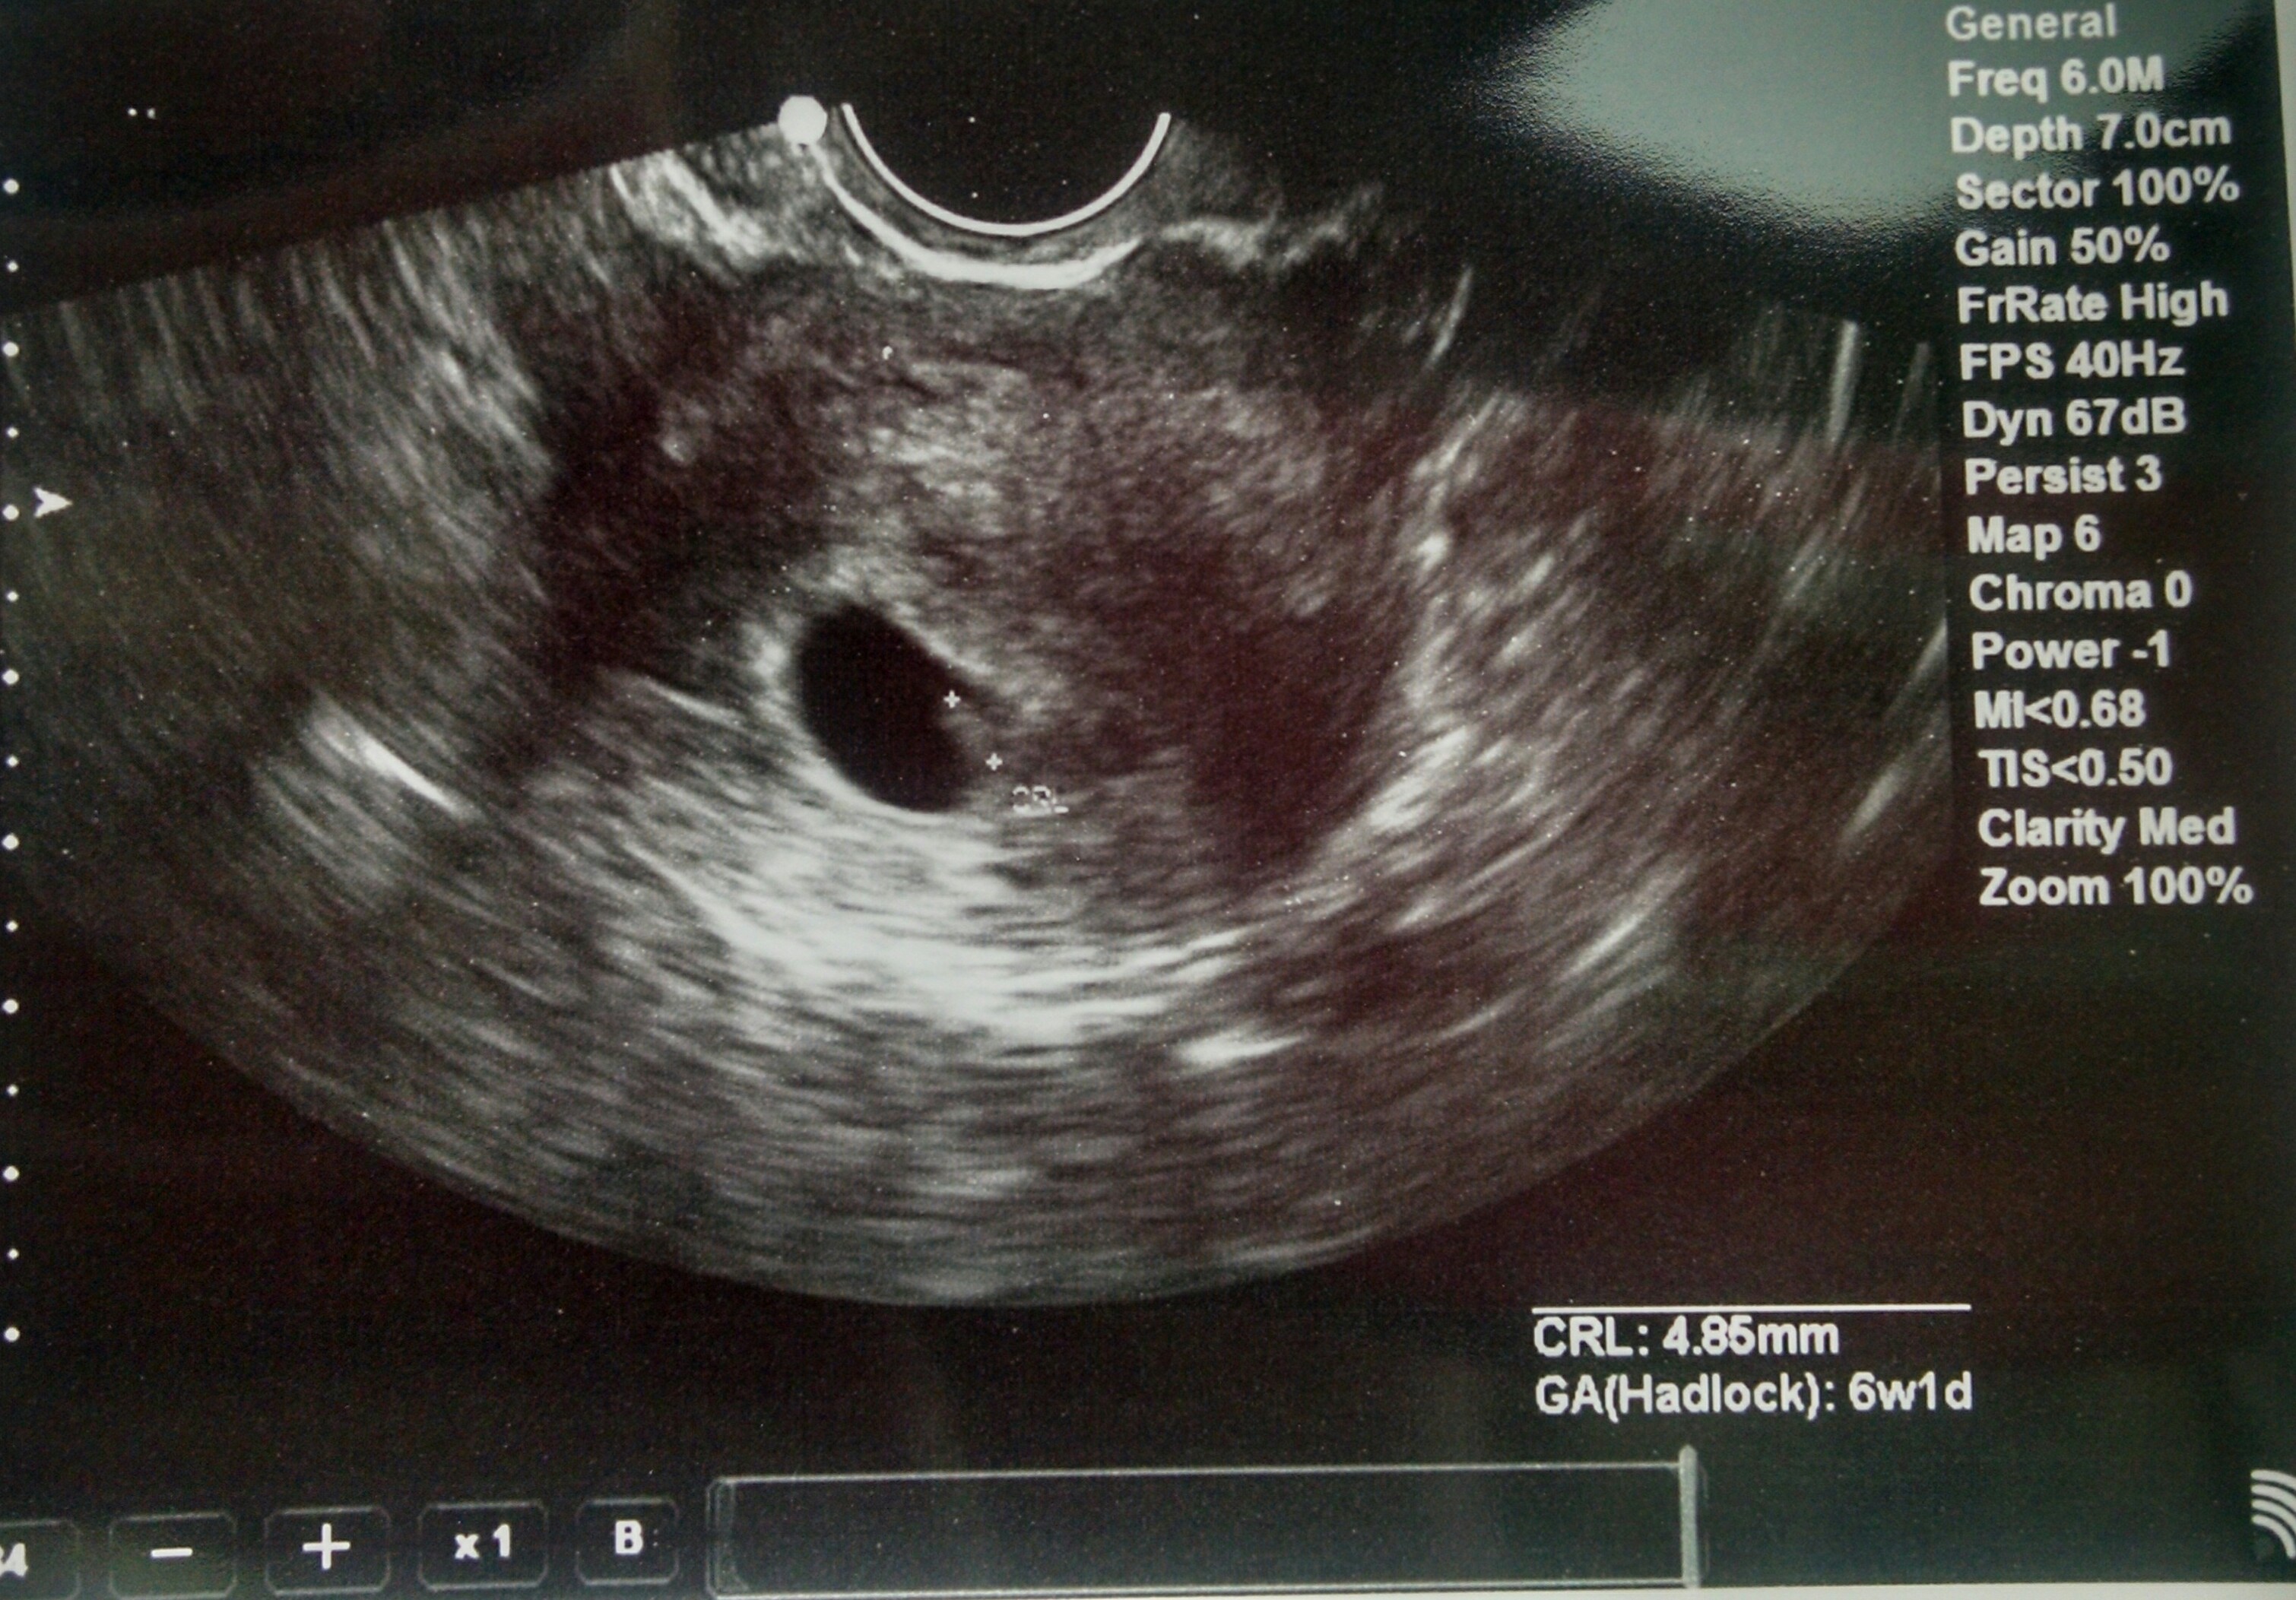

• First ultrasound today, measuring 6wks 4days just as we thought! Seeing that flicker of a heartbeat was such an incredible moment. Still on cloud 9! Congrats to everyone! !